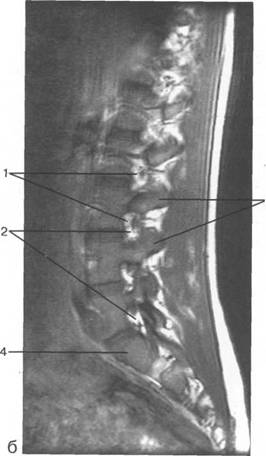

MPT. Cw_v.

V2; Th,; Thn;

ThXI1;

ThK-Thx.

Thlx; Thlx;